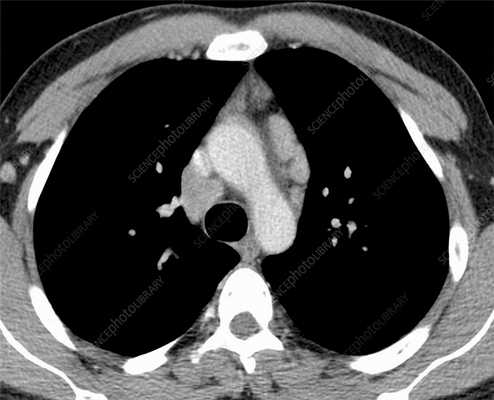

Посттрансплантационная лимфопролиферативная болезнь на рентгенограмме, КТ органов грудной клетки

Лимфома легких на КТ

Признаки лимфомы легких особенно выражены на четвертой стадии заболевания, когда болезнь поражает дыхательный орган. На КТ при этом будут видны увеличенные лимфоузлы, формирующие цепочки, конгломераты. При этом у пациента может также наблюдаться отек легких. Однако высокая разрешающая способность КТ позволяет выявить лимфому на ранней, первой стадии.

На КТ лимфомы, как и любые уплотнения, визуализируются сравнительно более светлым цветом. В норме воздушная легочная паренхима практически однородного темного цвета. Иногда таких уплотнений несколько и они диссеминированны. Контуры лимфомы четкие и ровные. Вокруг патологических очагов обнаруживаются участки «матового стекла».